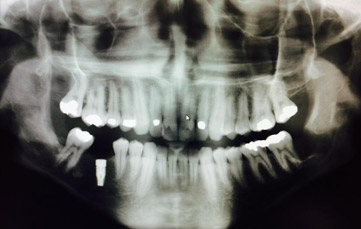

This patient presented to clinicians office for exam and possible removal of wisdom teeth 2008. There was an associated radiolucency with wisdom tooth right side. The patient was informed to wait for teeth to erupt or discomfort before removal.

The patient was lost to follow up and had no further Full images taken until 2012. There we can see radiolucency associated with right wisdom tooth extending completely ascending up right mandible approximately 6cm.The patient had an incisional biopsy under local anesthetic.In the differential diagnosis, a odontogenic keratocyst, central giant-cell granuloma, and unicystic ameloblastoma can mimic a dentigerous cyst. The return Diagnosis was Dentigerous Cyst. Rarely, some untreated dentigerous cysts develop into an odontogenic tumor (e.g., ameloblastoma) or a malignancy (e.g., oral squamous cell carcinoma). To avoid such complications, marsupialization and surgical enucleation of the cyst lining was the treatment of choice for this cyst.